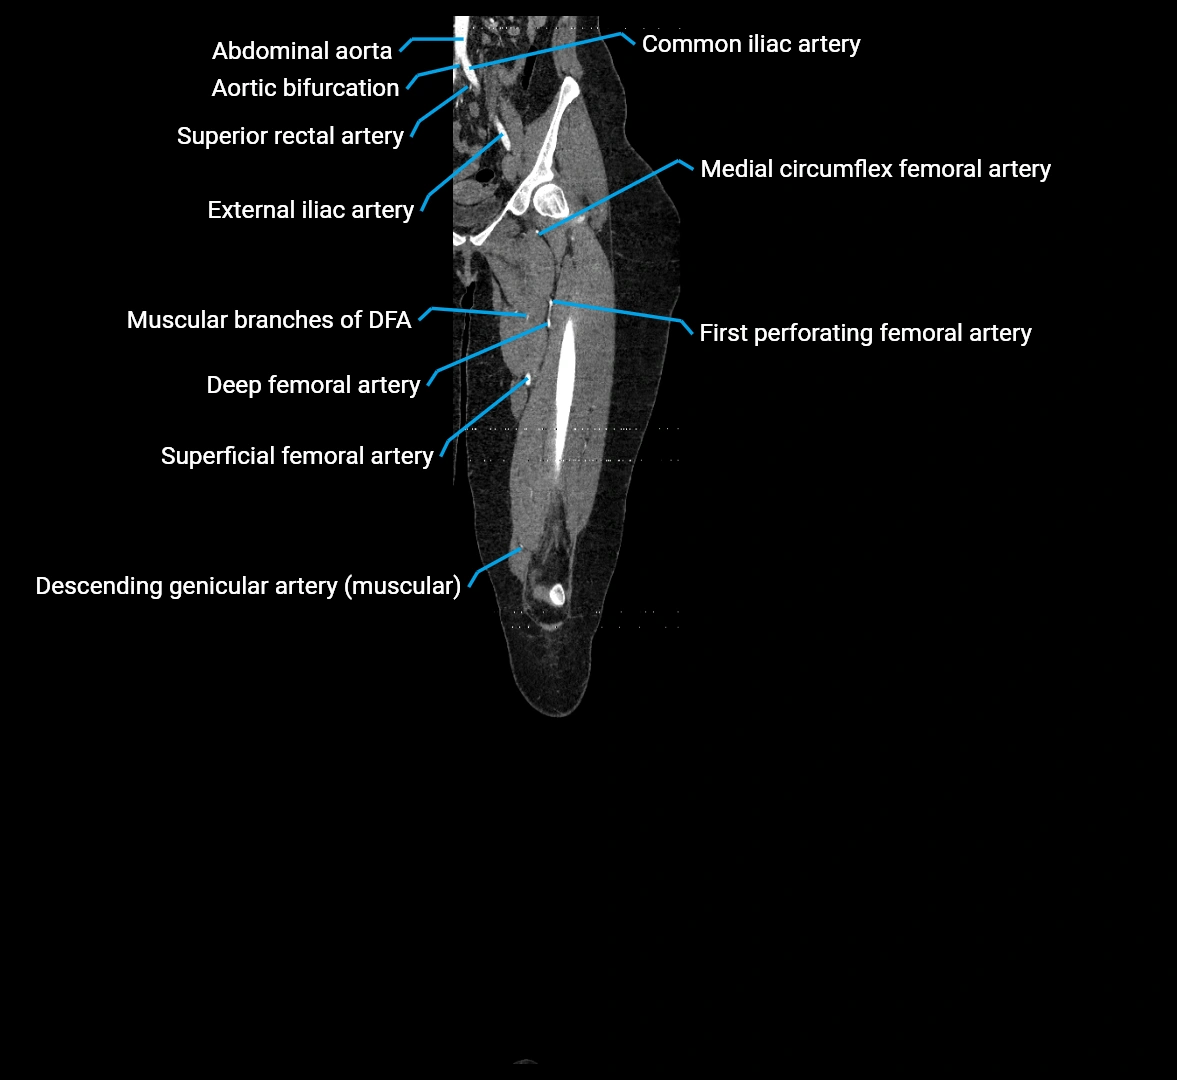

CT Appearance

Non-contrast CT:

• Appears as a tubular soft tissue structure anterior to vertebral bodies

• Calcified atherosclerotic plaques appear as hyperdense foci along the wall

• Useful for screening abdominal aortic aneurysm (AAA) size and mural calcification

Contrast-enhanced CT (CTA):

• Gold standard for abdominal aortic imaging

• Provides excellent detail of lumen, wall, aneurysm, thrombus, and branch vessels

• Multiplanar and 3D reconstructions help in aneurysm measurement, stent graft planning, and dissection evaluation

• Detects acute rupture, traumatic injury, or occlusion with high sensitivity

CT images

image